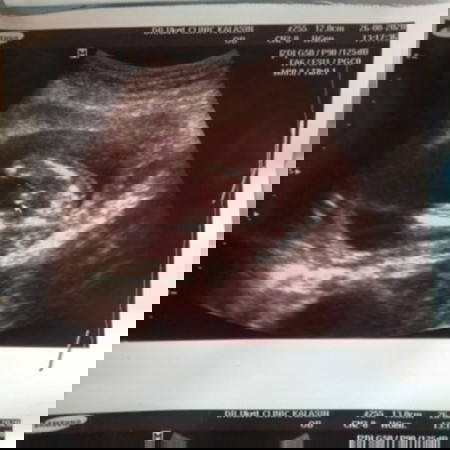

แม่ๆได้ลูกเพศไหนกันบ้างเอ่ย บ้านนี้ซาวด์ตอน16 w+6 จู๋ชัดมากค่ะของดูในซาวด์ขอแม่ๆหน่อยค่ะ

ตอน 16 วีคจ้า ตอนนี้ 18 แล้วจู๋ชัดมาก